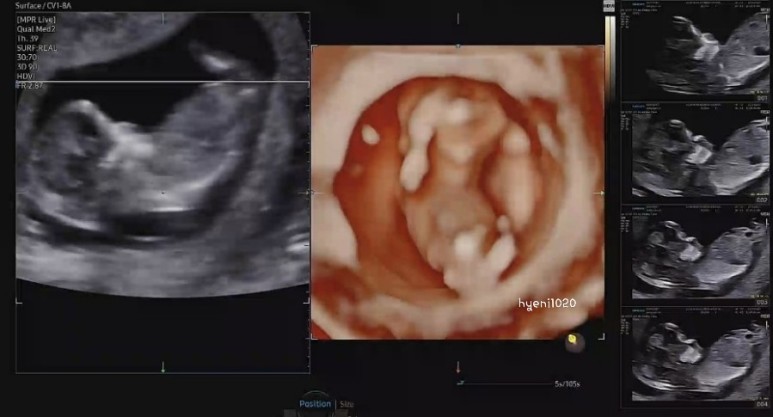

1차 기형아 검사

2차 기형아 검사를 받으러 간 날 상담했는데 갑자기 오늘 2차 기형아 검사를 하면서 취약성 X 증후군을 같이 검사하겠다고 하셨다.검사비는 105,000원이 추가된다.이번이 아니면 검사할 수 없다고 하셨는데 담당 선생님께서 다음에도 언제든지 검사할 수 있다고 하셨다.담당 선생님과 이야기하고 결정하기로 했다.

“채움검사 결과 저위험군으로 건강하게 태어나길❤❤”

검사 결과 저위험군으로 취약X증후군은 검사하지 않았다!